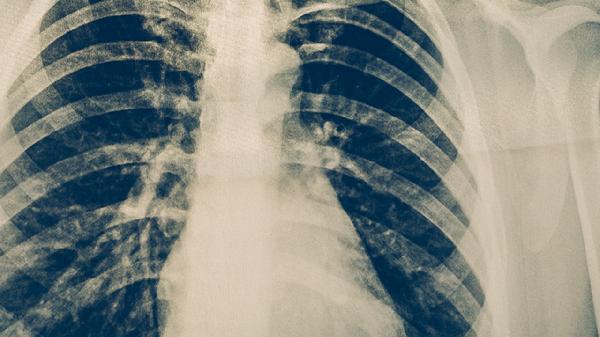

肺结核活动期可能因肺部组织坏死侵蚀血管导致咳血。典型表现为痰中带血丝或少量鲜红色血液,可能伴随低热、盗汗。需复查胸部CT评估病灶范围,医生可能调整抗结核药物组合,如异烟肼片、利福平胶囊、吡嗪酰胺片等,必要时联合止血药物。

3. 支气管血管损伤

结核杆菌感染可导致支气管黏膜溃疡或形成假性动脉瘤,突发大量咯血风险较高。典型表现为鲜红色泡沫状血液,可能伴随呼吸困难。需紧急行支气管动脉栓塞术,同时静脉滴注垂体后叶素注射液控制出血。